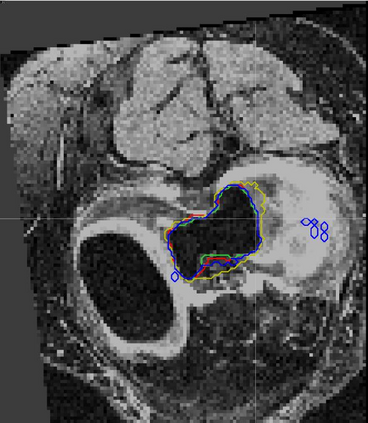

Direct automatic segmentation of objects from 3D medical imaging, such as magnetic resonance (MR) imaging, is challenging as it often involves accurately identifying a number of individual objects with complex geometries within a large volume under investigation. To address these challenges, most deep learning approaches typically enhance their learning capability by substantially increasing the complexity or the number of trainable parameters within their models. Consequently, these models generally require long inference time on standard workstations operating clinical MR systems and are restricted to high-performance computing hardware due to their large memory requirement. Further, to fit 3D dataset through these large models using limited computer memory, trade-off techniques such as patch-wise training are often used which sacrifice the fine-scale geometric information from input images which could be clinically significant for diagnostic purposes. To address these challenges, we present a compact convolutional neural network with a shallow memory footprint to efficiently reduce the number of model parameters required for state-of-art performance. This is critical for practical employment as most clinical environments only have low-end hardware with limited computing power and memory. The proposed network can maintain data integrity by directly processing large full-size 3D input volumes with no patches required and significantly reduces the computational time required for both training and inference. We also propose a novel loss function with extra shape constraint to improve the accuracy for imbalanced classes in 3D MR images.